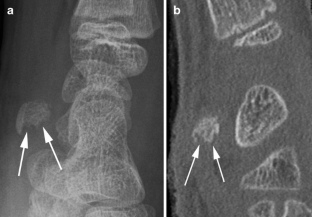

Fig. 1